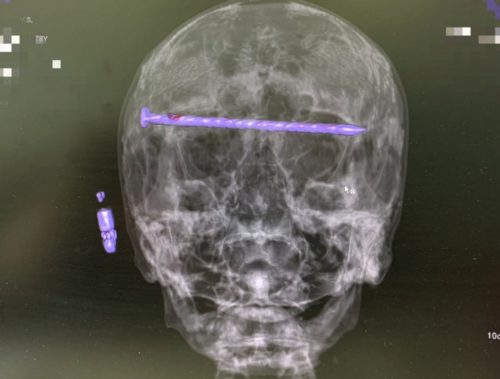

Нижнетагильские врачи в результате сложнейшей операции достали из головы 78-летнего пациента 15-сантиметровый гвоздь.

Мужчина поступил в приёмный покой Городской больницы №1 Нижнего Тагила в тяжёлом состоянии. На КТ медики увидели в костях черепа гвоздь, который прошёл через обе глазницы от правого до левого виска. Длина его достигала 15 сантиметров. Ситуация осложнялась повреждением твёрдой оболочки мозга и сдавлением глазных яблок.

Чтобы спасти пациента, бригада специалистов во главе с заведующим нейрохирургическим отделением ГБ №1 Нижнего Тагила Дмитрием Неволиным провела экстренную операцию. Гвоздь извлекли, сохранив мужчине и жизнь, и зрение.

Прооперированный мужчина под наблюдением бригады врачей быстро восстанавливается. Для профилактики осложнений он проходит антибактериальную терапию.